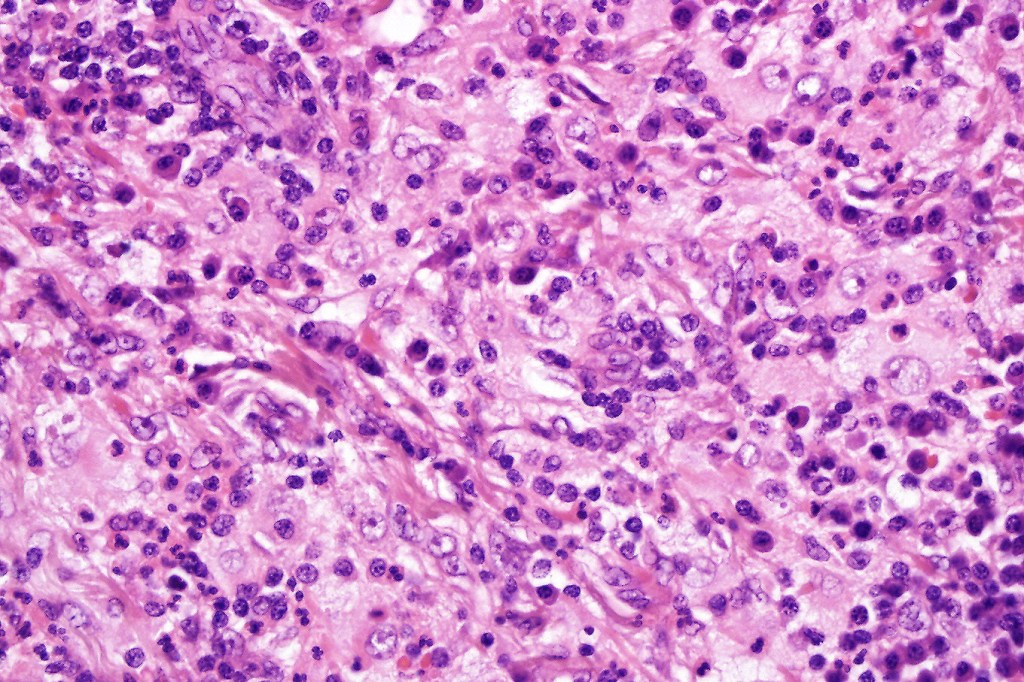

•Histiocytes are large with irregular borders and abundant cytoplasm

• Vesicular nuclei with a prominent nucleoli

•Emperipolesis of lymphocytes, plasma cells & neutrophils

•Background population of lymphocytes, plasma cells, neutrophils, eosinophils & variable numbers of xanthoma cells